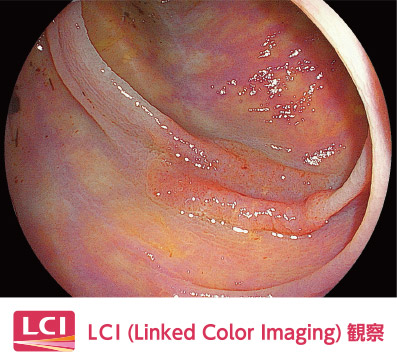

照射した光と画像処理を組み合わせる「マルチライトテクノロジー」により、粘膜表層の微細な血管や構造を強調するなど、目的に応じた観察画像を作り出す4色のLED光源搭載の内視鏡システム『ELXEO7000』を導入しています。

短波長狭帯域光と白色光の成分をバランスよく照射。そのあとソフトウェアにより、赤みを帯びた色はより赤く、白っぽい色はより白くなるように色の拡張・縮小を行い、粘膜の微妙な色の違いを強調します。これにより腫瘍や炎症の検出が容易となり、通常観察と比べ1.67倍上部の腫瘍性病変の拾い上げが可能と報告されました(多施設無作為比較試験LCI-FIND試験より)。